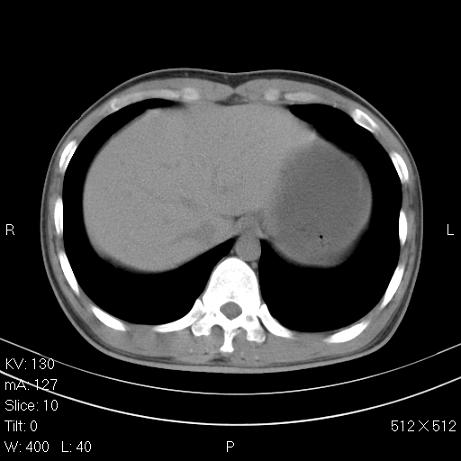

治疗后2周复查,请讨论

结合以前的ct片,还是考虑肺挫伤,吸收多了。

支持:创伤性湿肺。现肺挫裂伤(出血 积气)大部分吸收。建议继续治疗!

结合以前的ct片,支持创伤性湿肺。现大部分吸收。

支持:创伤性湿肺、肺挫裂伤。现肺挫裂伤(出血、渗出、液气腔)大部分吸收。建议继续治疗!

支持:创伤性湿肺、肺挫裂伤。现肺挫裂伤(出血、渗出、液气腔)大部分吸收.

结合老片支持创伤性湿肺、肺挫裂伤。

经治疗后病灶明显吸收,考虑创伤性湿肺、肺挫裂伤